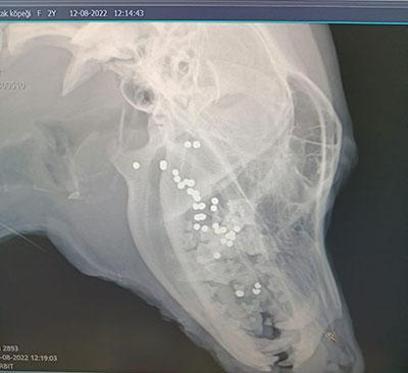

Antakya ilçesi Kisecik Mahallesi’ndeki sokak hayvanlarını düzenli olarak besleyen öğretmen Fatma Betül Yalım'ın 'Lili' ismini verdiği köpeğe önceki gece kimliği belirsiz kişilerce ateş edildi. Köpek ağzından yaralanırken, mahallelinin fark edip bilgi verdiği Yalım, dün sabah saatlerinde bölgeye gitti. Yalım, yaralı köpeği veterinere götürdü. Köpeğin dilinin koptuğu, ağzının içerisinde müdahale edilemeyecek durumda saçmaların bulunduğu tespit edildi.

Yalım, "vatandaşlar Lili’nin ağzından kan gelir vaziyette hareketsiz yattığını söyledi. Olay yerine gittiğimde araba çarptığını düşündüm. Lili’yi alarak hemen veterinere götürdüm. Orada çekilen röntgende olayın korkunç bir vahşet olduğunu anladık’’ dedi.

"Veterinerimiz yaptığı incelemede olayın gece saatlerinde olduğunu tahmin ediyor. Bir cani savunmasız köpeğin ağzının içine tüfeği yerleştirerek ateş ediyor. Dili kopan köpeğin ağzının içinde çok sayıda saçma tespit etti. Şu an yoğun bakımda. Kopan dilinin kalan kısmı dikildi. Ağzının içindeki saçmalara müdahale edilemiyor. Yaşam savaşı veriyor. Hayatta kalırsa bir daha normal beslenme yapamayacak. Su bile içemeyecek.’’